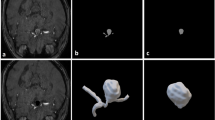

Throughout our experiments, the XGBoost model, trained with hyperparameters that included a learning rate of 0.1, maximum depth of 4, minimum child weight of 4, and subsampling rate of 0.8, exhibited the best performance. This performance was measured by the area under the receiver operating characteristic curve (AUROC), with the highest AUROC being 0.765 for the test dataset3. The feature importances of the variables applied to the model are summarized in Fig. 1.

Feature importance scores of the model. The length of the bar represents the score, and the length of the line indicates the 95% confidence interval. BMI body mass index, HTN hypertension, TOT_CHOLE total cholesterol, WAIST waist circumference, SMK_STAT_3.0/2.0 current/ex smoker, HMG hemoglobin, BP_HIGH/BP_LWST systolic/diastolic blood pressures, BLDS fasting glucose, Pulse pulse pressure, FMLY_HPRTS/HDISE/DIABML/APOP familial history of hypertension/heart disease/diabetes/stroke, DM diabetes.